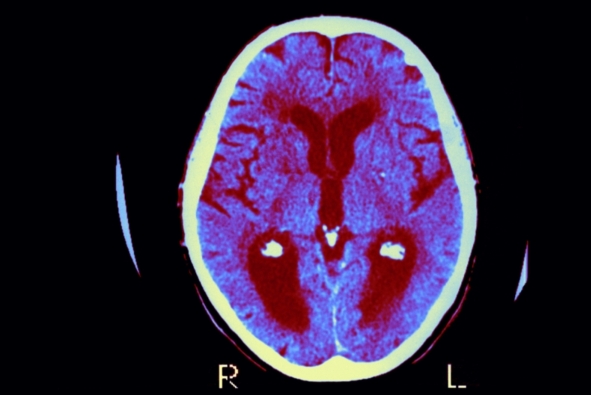

阿尔茨海默病是一种毁灭性的疾病,目前已有超过500万美国人因此丧失了认知能力和记忆功能,而科学家们一直以来都对其发病根源感到困惑不已。但是在一篇即将发表在《Journal of Alzheimer is Disease》上且颇引争议的社论中,一批科学家提出导致这一复杂疾病的病因可能很简单:就是一些能引起脑部感染的微生物。这一引人争议的观点并不新奇,长久以来学界都认为它太过荒诞而不予理会,但是越来越多的工作指出这可能是一个值得考虑并深入研究的方向。如果研究人员能证明这一理论,并且能够解释先前引发争议的某些细节(这两项任务都很艰巨,因为有关脑部感染的研究困难重重),那么人们便能从根本上阻止这一疾病的发生。

在到底哪种病原体可能触发阿尔茨海默病这个问题上,Tanzi认为HSV-1是一个备选答案,但是现在下定论还为时尚早。“我认为我们应该往回看几步,比如说‘哪种细菌,病毒或者真菌会随着我们变老而不断在脑部积累?’并且我们应该以一种客观的,怀疑的态度来系统地研究这一问题,”他谈到。Tanzi现在正领导着由治愈阿尔兹海默基金会(Cure Alzheimer's Fund)资助的一个团体(该基金会是一个非盈利机构),这个团体意图对人脑中的微生物组进行匹配;他认为,一旦发现具有潜在重要意义的微生物,那么就有可能开发活体人脑中的神经成像技术(neuroimaging techniques)来对它们进行追踪。